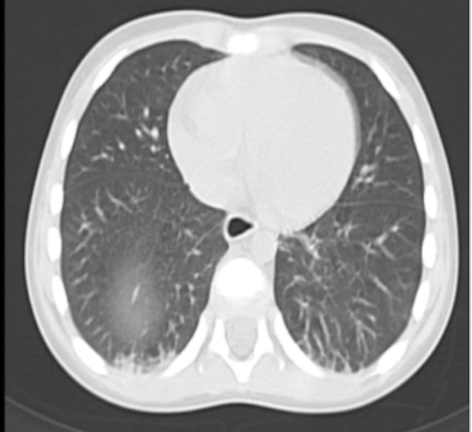

Per documentare la localizzazione del tumore, la sua estensione ed eventuali processi metastatici, si esegue TC encefalo, torace e addome. Si apprezzano, a livello toracico, una formazione solida dotata di enhancement in sede subpleurica apicale destra, area a vetro smerigliato al segmento posteriore del lobo superiore destro (entrambe ascrivibili a localizzazione di malattia; Figura 2) e alcuni linfonodi ingranditi in sede ascellare bilateralmente, mammaria interna destra (il maggiore di diametro 1,6cm) e in sede succlavia destra, tutti con enhancement. A livello addominale, si evidenzia altra formazione solida (3,5x2,3 cm). Non si evince invece dagli esami eseguiti (TC encefalo e rachicentesi) coinvolgimento cerebrale. La visita cardiologica risulta nella norma, tranne che per un difetto del setto interventricolare muscolare con minimo shunt sinistro-destro, già noto e in follow-up. L’aspirato midollare non evidenzia blasti e negativa è la ricerca della traslocazione t (8;14).